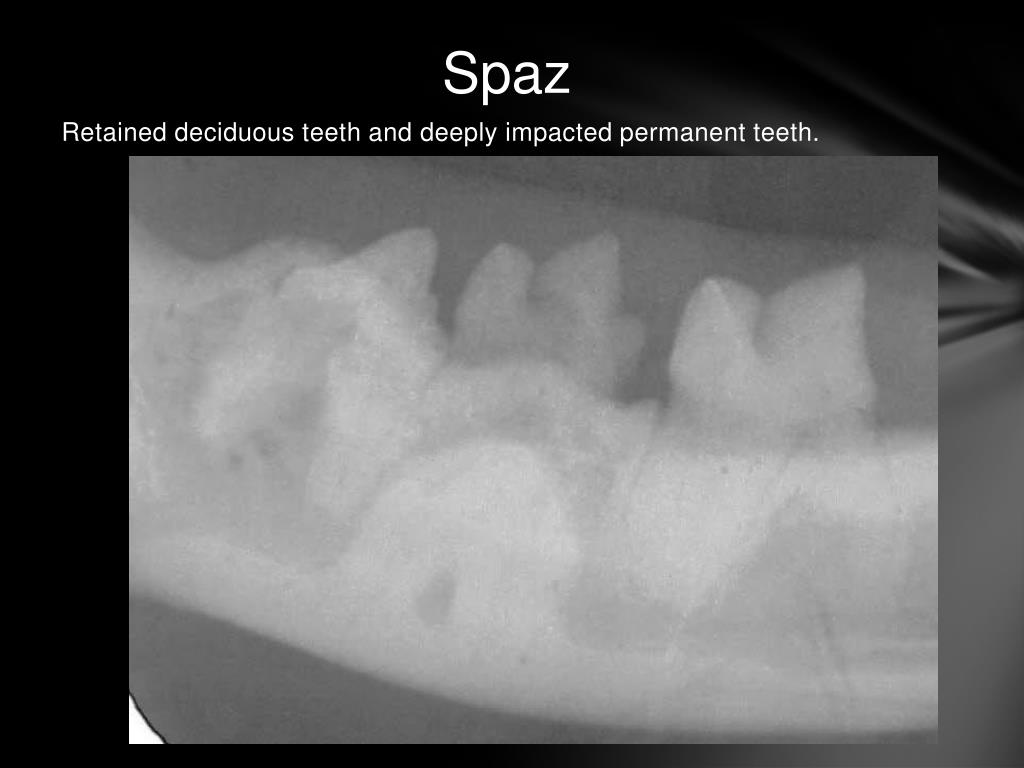

Teeth And Knees Cats . Previously, it was reported as feline knees and teeth syndrome. It is hypothesized that affected cats have a metabolic defect that. 1 current evidence suggests a heritable component; Cats with persistent deciduous cheek teeth should be closely monitored, as pathologic. Patellar fracture and dental anomaly syndrome (pads), formerly known as knees and. The feline knees & teeth syndrome is a newly recognized pattern of developmental dental and orthopedic pathologies. Feline knees and teeth syndrome should be considered in cats that have spontaneous onset of pelvic limb lameness. Did you know that 70% of cats will experience oral/dental problems before the age of 3? Affected cats prone to pathological fractures. Be prepared by learning to recognize these 10 signs of cat tooth pain! Lameness, discharging sinuses around the mouth and chin, mandibular (and maxillary) osteomyelitis, persistent nail bed infections. Patellar fracture and dental anomaly syndrome (pads) is a rare but recognized syndrome in cats, formerly colloquially known as “knees and.